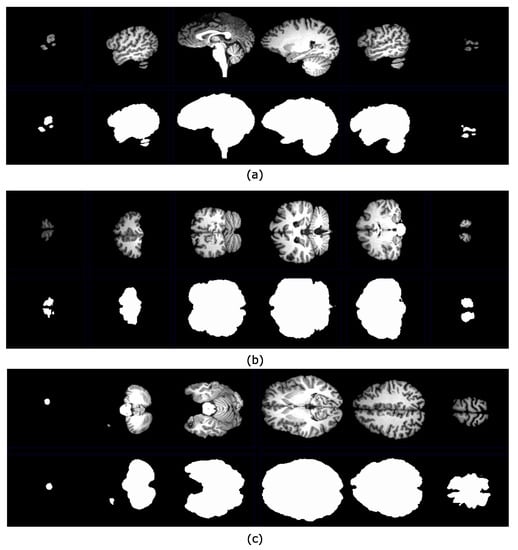

4.1. Brain Extraction Based on the Maximum Hyperconnected Function

4.2. Brain Extraction Based on Hyperconnected Functions and Lower Leveling